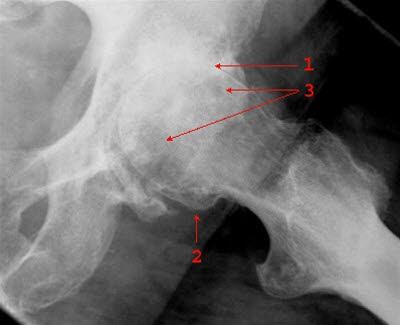

Betydelig mer artroseforandringer i venstre hofteledd.Hofteleddet består av hofteskåla, som er en del av bekkenbeinet, og lårbeinets hoftekule. Både hofteskålen og hoftekulen er "kledd" med glatt brusk som sikrer at bevegelser foregår med minst mulig motstand.

Startsmerter ved gange som blir bedre, for så å forverres ved fortsatt gange, er svært typisk for diagnosen. Ved undersøkelse av hoften finner legen at bevegeligheten er nedsatt, særlig ved rotasjon innover og utover. Blodprøver har ingen betydning for å stille diagnosen. Røntgenbilder av hoften viser karakteristiske forandringer og bekrefter diagnosen.